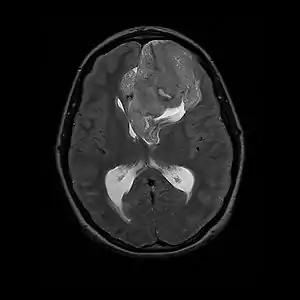

Neurocytoma

Neurocytoma is a type of nervous system benign tumor which is primarily derived from nervous tissue.[1]